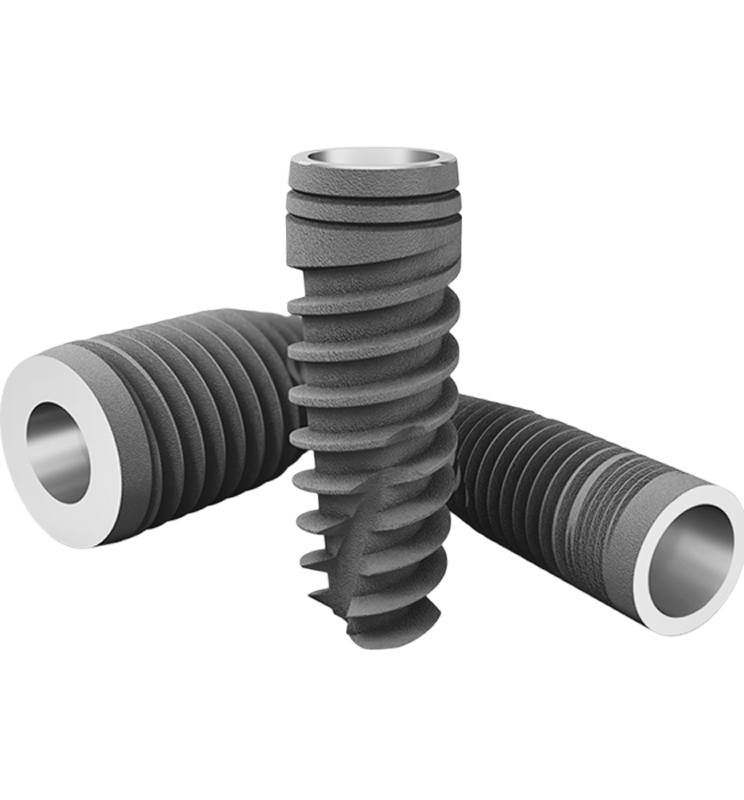

Advanced EV Implant System

Designed for immediate load

with functional Prosthesis.

Shorter Time to Teeth.